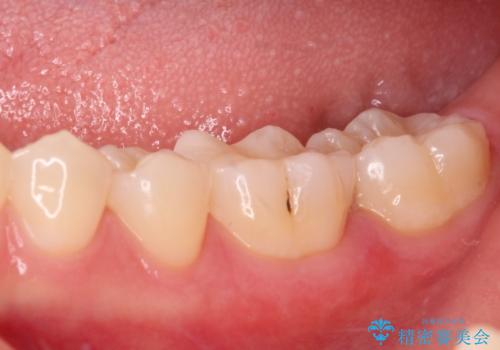

- 奥歯の銀歯と虫歯を気にして来院された患者様です。

下顎は口を開けたときに目立つためセラミックインレーに、上顎奥歯は機能面を優先してゴールドインレーにて修復治療を行うこととしました。

機能面を優先すると、PGAインレー(ゴールドインレー)による修復治療やPGAクラウンによる補綴治療が望ましいのですが、笑ったときに見えている銀歯がどうしても気なってしまうとのことで、目立ってしまう奥歯はセラミックインレーやセラミッククラウンを装着することとしました。